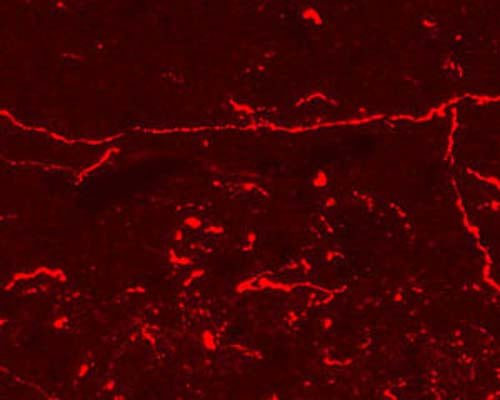

Immunohistochemical staining in rat ventral periaqueductal grey matter (PAG). 4% paraformaldehyde fixed rat brain crystostat sections (10 µm) were incubated overnight at 4°C with Rabbit polyclonal antibody to Endomorphin-1 and Endomorphin-2 (10 µg/mL) followed by incubation with donkey anti-rabbit Rhodamine Red conjugated secondary antibody (1:200).